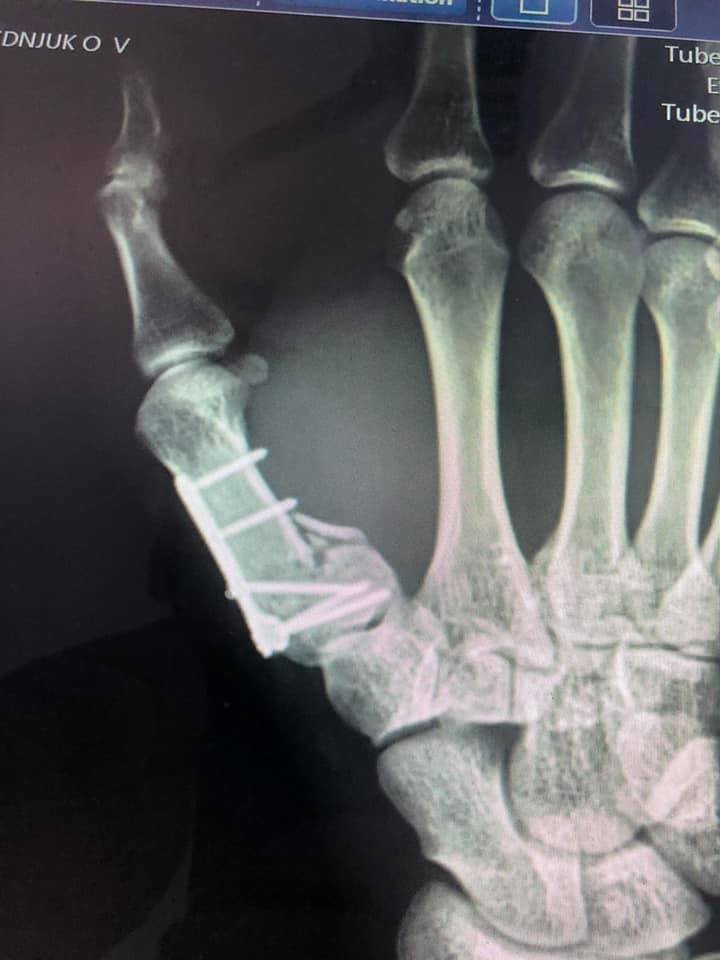

Волинянину провели оперативне лікування: остеосинтез п’ясної кістки та фіксацію титановою міні пластиною. Операція пройшла успішно.